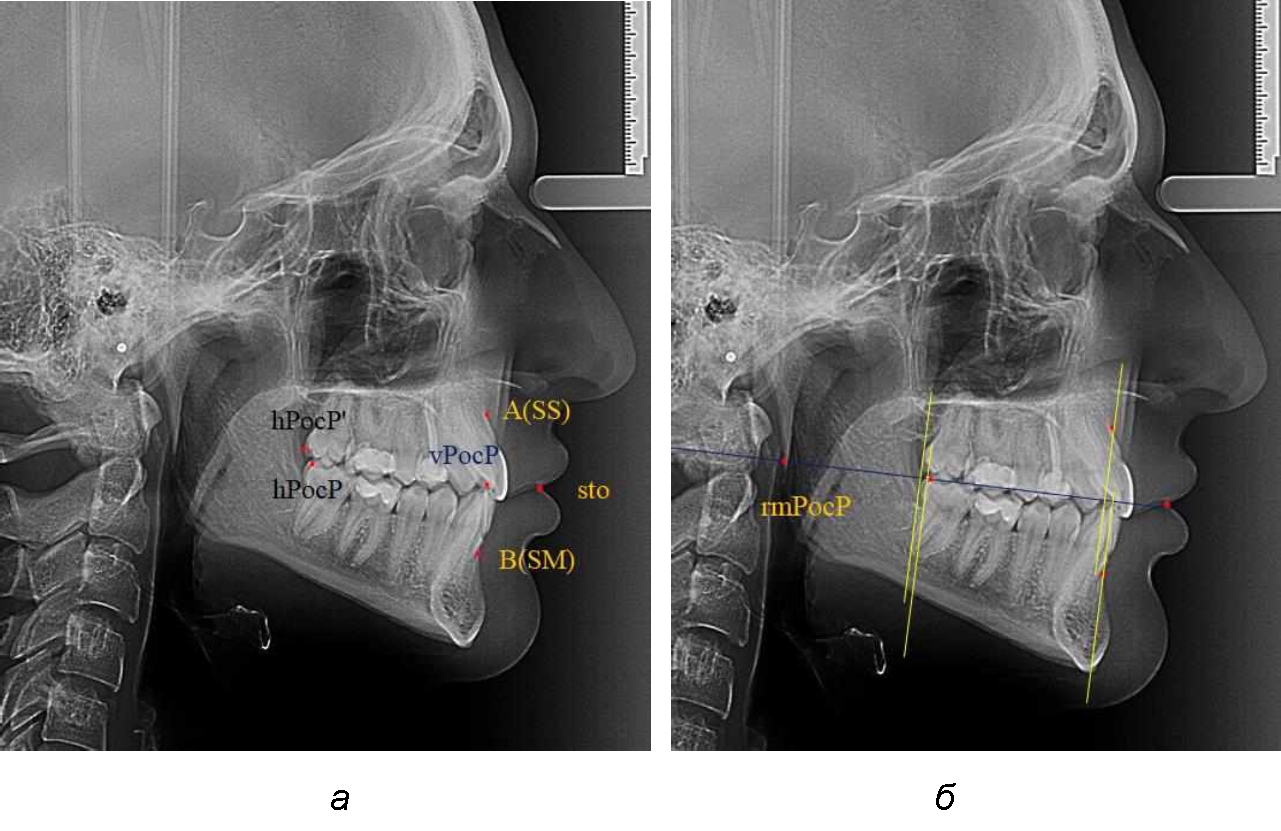

На рентгенограммах устанавливали точки Downs. На верхней челюсти субспинальная точка A(SS) располагалась в наиболее вогнутой точке альвеолярного отростка по переднему его краю. На нижней челюсти супраментальная точка B(SM) соответствовала месту наибольшей вогнутости переднего края альвеолярной части. Окклюзионную линию проводили через контактную точку резцов (vРOcP) и дистальную точку окклюзии второго нижнего моляра (hРOcP). Место пересечения окклюзионной линии с дистальным краем ветви нижней челюсти (ramus mandibule) обозначали как «rmРOcP». Перпендикулярно к окклюзионной плоскости проводили линии из точек «А(SS)» и «В(SМ)», что определяло их проекцию на окклюзионную линию. Аналогично отмечали положения дистальных окклюзионных точек верхней и нижней челюсти (рис. 1).

Рис. 1. Положение основных точек (а) и линейных ориентиров (б) для анализа положения и размеров челюстей

Альвеолярно-дентальный размер верхней челюсти и нижней челюсти оценивали по окклюзионной линии между вертикалями, ограничивающими исследуемые челюсти. Положение верхней челюсти оценивали по величине размера «rmOcP-А», а нижней челюсти по расстоянию «rmOcP-В». Линия смыкания губ обозначалась как точка «sto», вблизи которой проходила окклюзионная линия. Данный ориентир позволял провести окклюзионную плоскость при аномалиях положения резцов в вертикальном направлении, когда была сложность определения резцовой окклюзионной точки (vРOcP).

На рентенограммах с признаками дистальной окклюзии Wits-число имело положительные значения. Дистальная точка нижнего моляра была расположена позади верхней дистальной точки окклюзии второго моляра. Относительно равными, так же как и при анализе снимков с мезиальной окклюзией, считались показатели альвеолярно-дентальных размеров, при которых разница не превышала 1,5 мм. Тем не менее расстояние «rmРOcP-A(SS)» превышало расстояние «rmРOcP-B(SM)» в среднем по группе на (5,29 ± 1,47) мм (рис. 4).

Рис. 4. Положение апикальных точек и челюстей при дистальной окклюзии с равными (а) и разными (б) альвеолярно-дентальными размерами зубочелюстных дуг

В тех случаях, когда при дистальной окклюзии альвеолярно-дентальные размеры были различными, размер нижней челюсти превышал аналогичный параметр верхней челюсти, в среднем на (3,62 ± 1,12) мм.